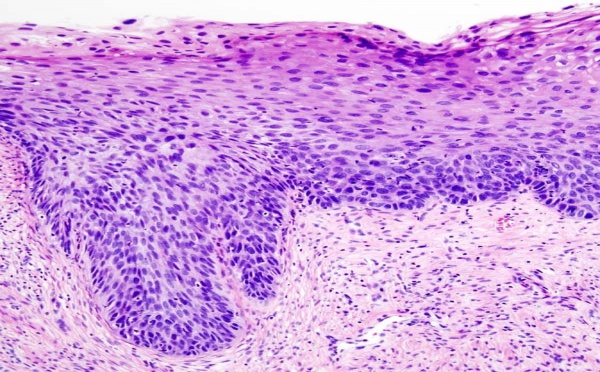

Utilizan la tecnología LED para tratar el cáncer cervical - 18/03/2011

Las compañías Sagentia y Photocure, especializadas en la tecnología de fototerapia dinámica, han desarrollado un dispositivo que cura el cáncer cervical en sus estadios iniciales, utilizando sólo una fuente de luz LED y un medicamento en forma de pomada.